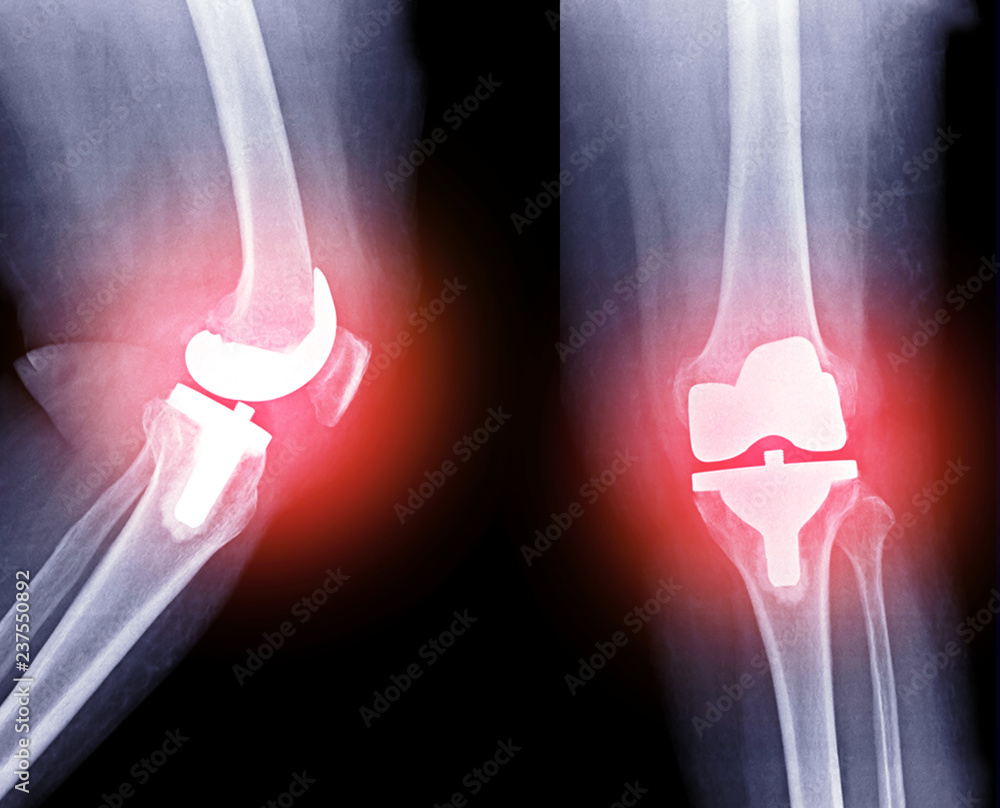

From stock.adobe.com

Xray image of Right knee joint replacement (red color glow)/ knee Knee Replacement Xr How to recover from a knee replacement. The surgeon makes a cut down the front of your knee and moves your kneecap to the side so. Total knee replacement surgery is usually necessary when the knee joint is worn or damaged so that your mobility is reduced and you are in pain even while resting. Knee replacement surgery (arthroplasty) involves. Knee Replacement Xr.